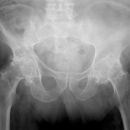

Becken / Hüfte

Coxarthrose